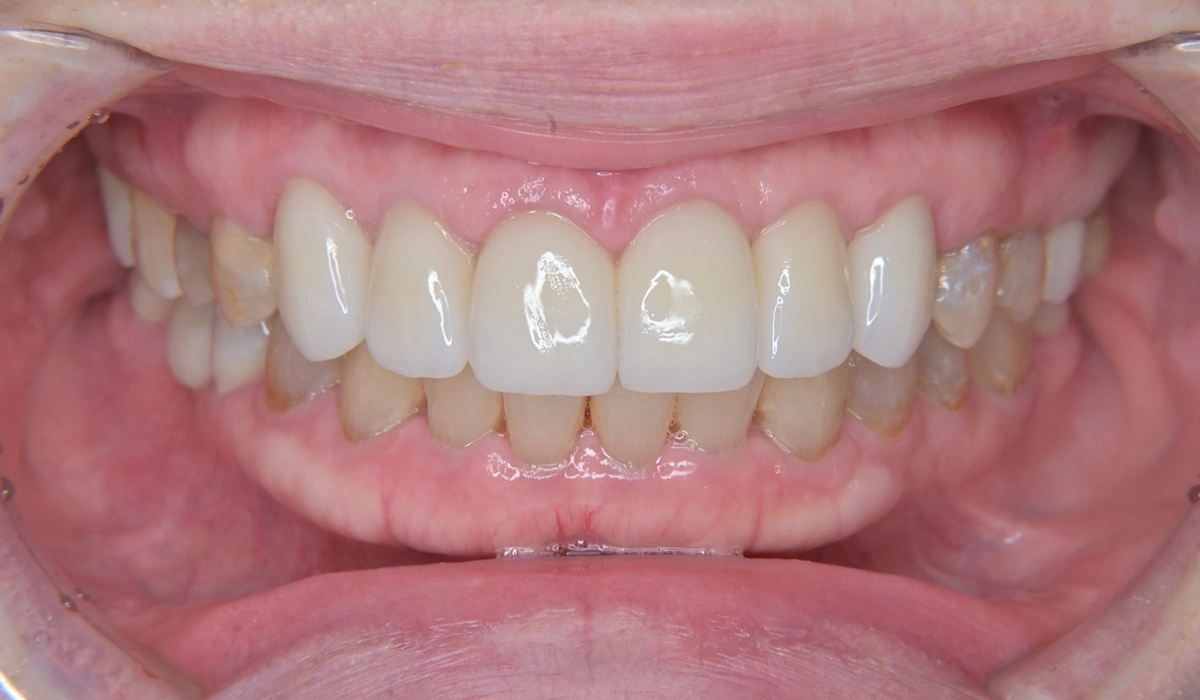

治療後の写真がこちらになります。

プロビジョナルレストレーションで問題点していたブラックトライアングルの問題が最終補綴物では修正できていることがわかります。

右上6と左下7はダイレクトボンディングにより必要最小限の切削介入で治療を行っています。右下6欠損部に対しては様々な治療選択肢のメリット・デメリットを考慮の上ジルコニアブリッジによる欠損修復治療を行いました。

本症例では術前に歯肉の形態や歯冠の最終形態を模型上で診査・診断をした上で治療を開始しました。審美的なゴールを設定しているため回り道をせずに一直線に思い描いていたゴールに到達することができました。

歯周環境については患者様とともに歯周基本治療により改善した状態を維持できており、今後も安定した歯周環境の維持に取り組みたいと考えています。